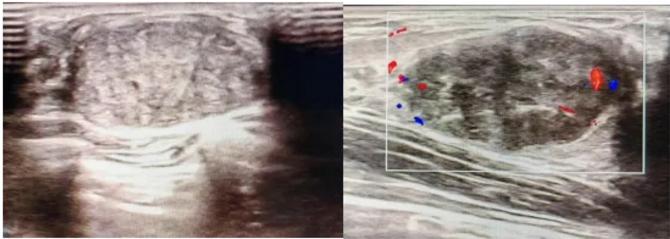

三、彩超檢查:無創(chuàng)檢查的“黃金眼”

高分辨率:可清晰顯示腫塊形態(tài)、血流信號,敏感度達(dá)80%-90%。

2.彩超報告關(guān)鍵指標(biāo)

形態(tài):良性多呈橢圓形或分葉狀,邊界光滑。

縱橫比: 良性通常<1(橫徑>縱徑) 。

血流信號:纖維瘤血流較少,惡性常伴豐富雜亂血流。

鈣化:粗大鈣化多為良性,細(xì)小簇狀鈣化需警惕惡性。

BI-RADS分級:2-3類提示良性,4類以上需進(jìn)一步檢查。

典型表現(xiàn):

橢圓形低回聲團(tuán)塊,包膜完整,內(nèi)部回聲均勻,后方回聲增強(qiáng),周邊無“蟹足樣”浸潤。